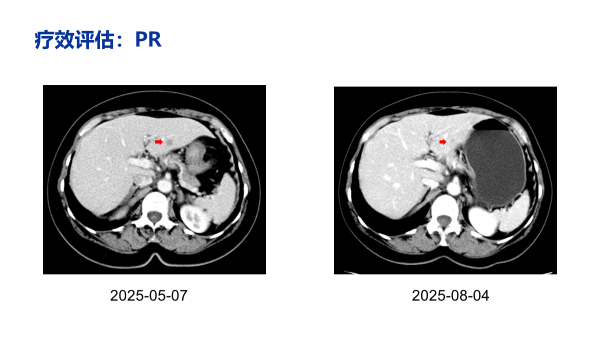

治疗近2个月后(2025-08-04),影像学评估疗效为部分缓解(PR),肝脏转移灶较基线明显缩小。

然而,有了精准的靶点,治疗方案的“有效性”与“安全性”便成为决定其临床价值的关键。该患者在选择一线三联方案后,肿瘤得到了快速的抑制,缩瘤效果显著,INAVO120数据中就显示了伊那利塞高效且持久的肿瘤控制:客观缓解率(ORR)从28.00%提高到了62.70%,比标准治疗组高出了一倍多。缓解持续的时间(DoR)也更长,达到了19.2个月。本例患者在短期内即获得PR,正是这一高效深层缓解能力的真实体现。